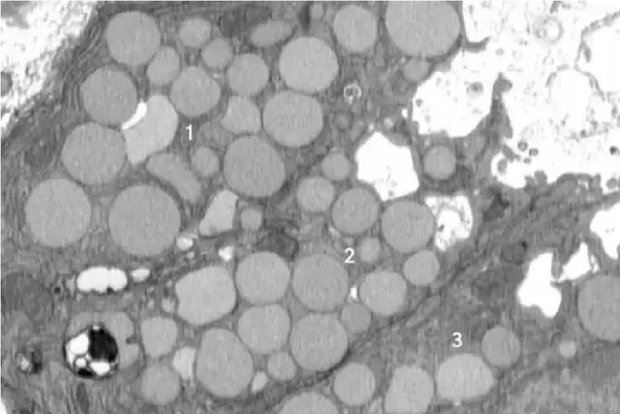

دکتر براون در طول تحقیقات مداوم خود متوجه وجود بقایایی در خارج از سلول‌ها در یک مدل آسیب معده در موش‌ها شد. او متوجه شد که با ادامه پخش شدن مواد زائد، اتفاقی عمدی در حال رخ دادن است. آسیب معده این اثر پاکسازی یا کاتارتوسیتوز را در پاسخ ترمیمی بزرگتر پالیژنوز ایجاد کرد. این زمانی است که یک سلول برای بهبودی به حالت سلول بنیادی برمی‌گردد.

وی افزود: بنابراین، این پاکسازی سلولی راهی سریع برای خلاص شدن از شر آن دستگاه است تا بتواند به سرعت به یک سلول کوچک و اولیه تبدیل شود که قادر به تکثیر و ترمیم آسیب باشد. ما این فرآیند را در دستگاه گوارش شناسایی کردیم، اما گمان می‌کنیم که در سایر بافت‌ها نیز مرتبط باشد.

اساساً سلول‌ها برای پاکسازی دستگاه سلولی خود، مواد زائد را استفراغ یا پاکسازی می‌کنند. این به عنوان یک میانبر عمل می‌کند که به آنها اجازه می‌دهد بافت سالم را سریع‌تر رشد دهند، زیرا روش معمول آنها برای تجزیه مواد زائد خیلی طول می‌کشد. با این حال، این عمل دارای معایبی است.